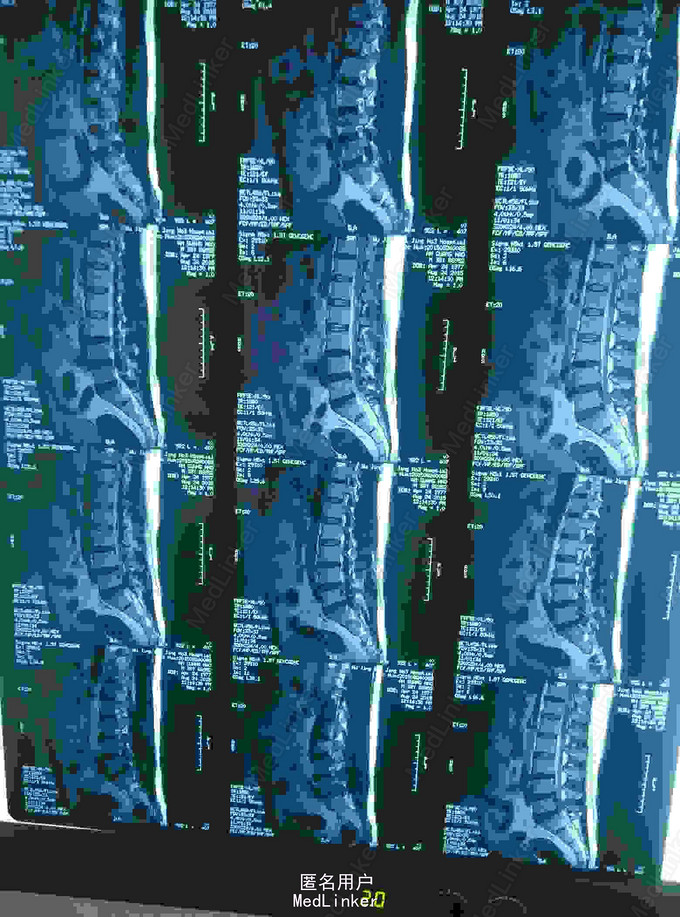

腰椎间盘突出

腰痛伴左下肢疼痛麻木3年

椎间盘突出穿破后后纵韧带游离到硬膜囊背侧

腰椎间盘突出,腰椎间孔镜治疗